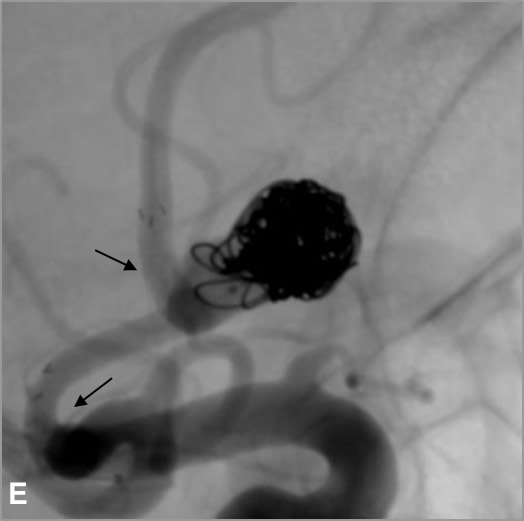

D, E, F: Tratamiento mediante “coiling”, inicialmente simple, posteriormente asistencia con stent mediante técnica “jailing” obteniendo compactación óptima de las espiras (las flechas negras indican las marcas radiopacas proximal y distal del stent; las flechas blancas muestran la permeabilidad de las arterias adyacentes al cuello aneurismático tras el tratamiento).

Ante la necesidad de implantación de stent se comenzó doble antiagregación una semana antes del tratamiento. Se inició el procedimiento mediante “coiling” simple, pero ante el riesgo de comprometer las arterias adyacentes se completó con “coiling” asistido con stent mediante la técnica “jailing”3, dejando el extremo distal del primer microcatéter en el interior del saco aneurismático interponiéndolo entre la malla del stent y la pared arterial. Tras desplegar el stent (Neuroform Atlas®) se completó el tratamiento, consiguiendo una compactación óptima de los “coils”, y evitando la protrusión de espiras que pudieran comprometer las ramas arteriales adyacentes, de especial interés en este caso.